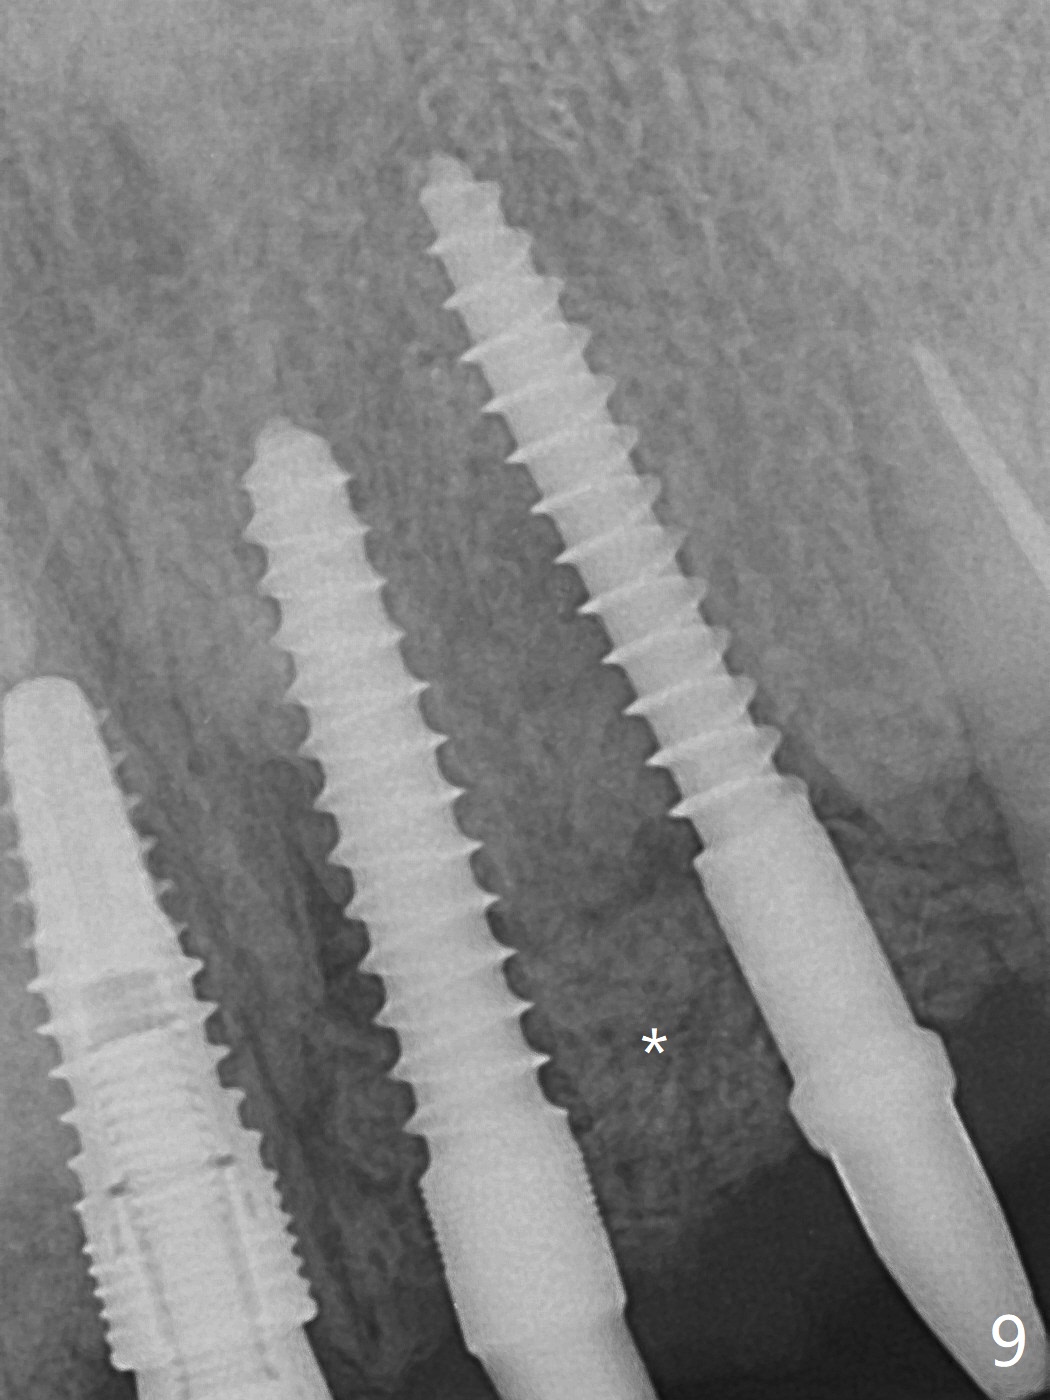

Incision shows exposure of microthreads at #9 and major threads at #10 due to buccal placement (Fig.1). There is bone palatal to the implant at #10 (Fig.2 P), to which a new implant will move. After implant removal, a narrower 1-piece implant (2.5x14(4) mm) is placed palatally at #10 (Fig.3,4) in combination of guide and free hand. At the site of #9 after implant removal, the guide is not used; a 3x17 mm angled 1-piece implant is placed with bad trajectory (Fig.5,6). After re-adjustment (Fig.7), the implant is placed at the right orientation (Fig.8). It appears that the guide is helpful. Allograft is placed mainly buccally (Fig.9,10 *), followed by a piece of collagen membrane (Fig.11). After tension release, flaps are approximated (Fig.12). The buccal gingiva at #9 and 10 recede nearly 2 months postop (Fig.13). Less recession at #9 is associated with more inflammation (Fig.14). The margin of the provisional is adjusted for gingival margin down growth and easy self cleaning with Water Pik (Fig.15). One month later, the gingival inflammation reduces, while there is no obvious buccal collapse (Fig.16,17). Impression is taken after laser gingivectomy nearly 4 months postop (Fig.18). While the gingiva around the implant at #9 is inflamed (periimplantitis?), the gingival cuff at #10 is well formed 5.5 months postop immediately before cementation (Fig.19). The buccal concavity at #10 is minimal (Fig.20). The gingival inflammation at #9 will be hopefully resolved after cementation of the final restorations (Fig.21). There appears to be new bone formation around the coronal implant threads 5.5 months postop (immediately post cementation, Fig.22). The microthreads at #9 may be not covered by the bone, the reason for the gingival erythema. The redness at #10 is asymptomatic 5.5 months post cementation (Fig.23). 粘固后两年牙槽嵴骨质并没有再生(图二十四),说明第一术中植体必须植入骨下(基台部分要长,否则难于修复),第二牙槽嵴处不应该有压力,植入2.5毫米植体,最后钻头应该是2.5毫米,骨下1-3毫米(尝试项目)。